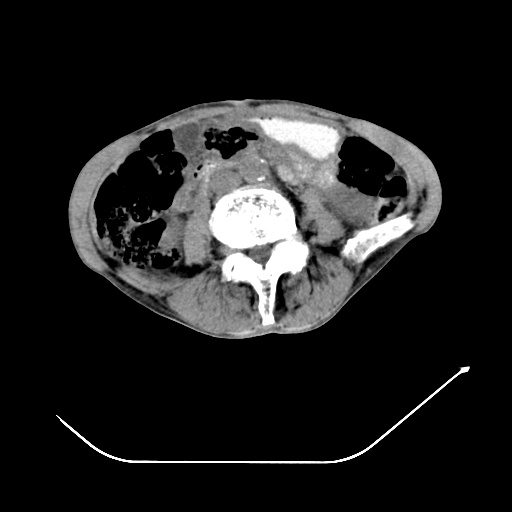

以下是引用zsl6918在2008-8-25 21:55:00的发言:[br]符合右肺周围性肺癌并肺内转移,左肺结核球。双肺肺气肿。腰椎附件转移。

以下是引用随光逐影在2008-8-25 22:03:00的发言:[br]1)考虑右肺下叶周围性肺癌并肺内转移,腰椎附件转移。2)左上肺结核(结核球形成)。3)双肺肺气肿(多发肺大泡形成)。4)双肺门区及纵隔内多发淋巴结钙化。

以下是引用qc80012345在2008-8-26 6:14:00的发言:[br]符合右肺周围性肺癌并肺内转移,左肺结核球。双肺肺气肿。腰椎附件转移。